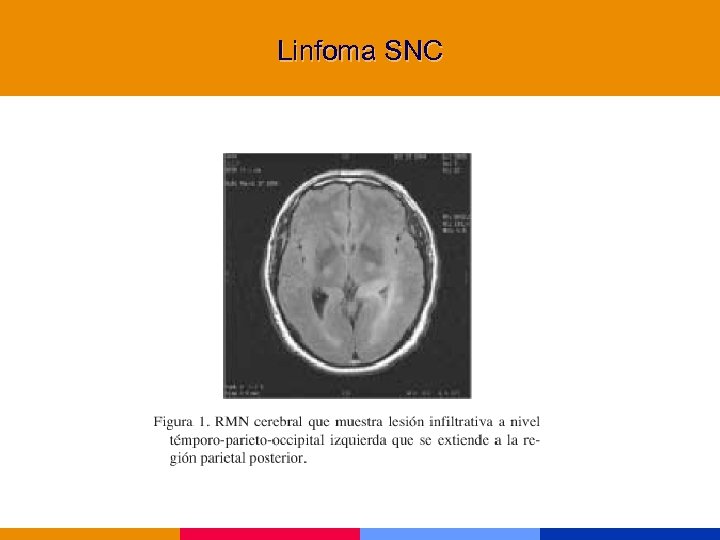

Linfoma § Inmunocompromiso severo. § Confusión, trastornos mnésicos, foco, convulsiones, pares craneanos. § Lesiones hipodensas que refuerzan contraste. Gralmente. únicas (50% múltiples en RMN). § Asociado a EBV. Detección en biopsia o LCR. § Trat. : radioterapia

Linfoma § Inmunocompromiso severo. § Confusión, trastornos mnésicos, foco, convulsiones, pares craneanos. § Lesiones hipodensas que refuerzan contraste. Gralmente. únicas (50% múltiples en RMN). § Asociado a EBV. Detección en biopsia o LCR. § Trat. : radioterapia

Linfoma primario SNC

Linfoma primario SNC

Linfoma SNC

Linfoma SNC

Linfoma SNC

Linfoma SNC